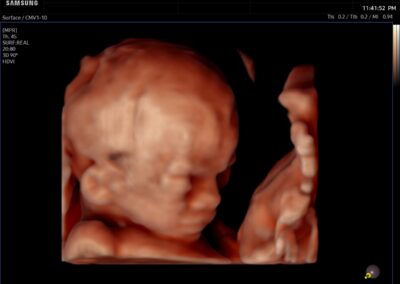

Comprehensive, advanced and expert MFM care for high-risk pregnancies

- Fetal anomalies